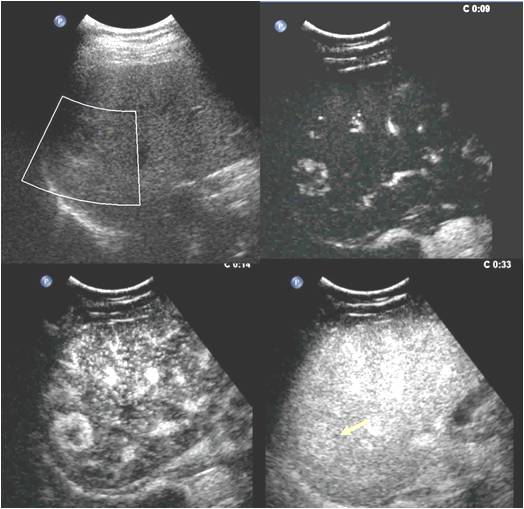

图1

图1和图2分别为两例肝脏占位性病变,仅凭二维和彩色多普勒超声无法定性,分别作了超声造影检查,根据病灶增强模式等超声造影特点,诊断出图1中的病灶为良性的血管瘤,临床上观察即可,而图2中的病灶为肝细胞癌,临床需要手术等治疗。